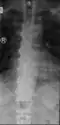

Confluent ossification of multiple contiguous vertebral bodies in diffuse idiopathic skeletal hyperostosis (DISH) -

Ossification of the posterior longitudinal ligament in DISH -